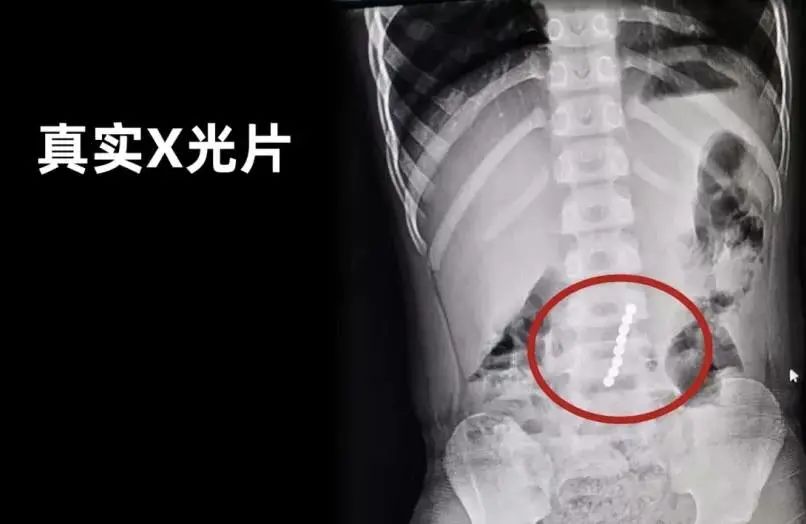

專家介紹,如果兒童吞食兩個及兩個以上的強力磁鐵,或者吞食強力磁鐵和其他磁性物體(鐵、鈷、鎳),磁鐵會在消化系統(tǒng)中與另一個磁鐵(或鐵磁性物體)吸附,并對腸壁產(chǎn)生壓力。

簡要說,就是磁力珠磁力強大,即使隔著腸道也能黏在一起,影響腸胃的正常蠕動,甚至擠壓黏膜,導(dǎo)致黏膜缺血,嚴重時可能會造成腸梗阻,腸穿孔等。如果不小心誤食或者塞入體內(nèi),想要取出來有的需要緊急做腸鏡,有的則只能做開腹手術(shù)!

最可怕的是,磁力珠丟幾個一時半會也發(fā)現(xiàn)不了,很可能延誤了最佳治療時間。